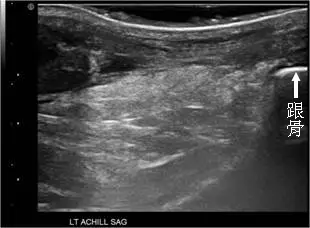

57 歲女士主訴下樓梯時,突然左腳後跟劇烈疼痛,隔天至骨科門診,接受腳後跟超音波檢查矢狀切面如圖,最可能之診斷為何?

阿基里斯腱(Achilles tendon)完全斷裂(rupture)在超音波矢狀切面(sagittal view)下呈現特徵性的「纖維不連續」與「低回音間隙(gap sign)」,可與跟腱炎(tendinitis)、纖維瘤(fibroma)及後跟滑囊炎(retro-calcaneal bursitis)做出鑑別。本題患者為 57 歲女性,下樓梯時突然發生劇烈後跟疼痛,是阿基里斯腱斷裂的典型受傷機制。

影像分析:

本題附有兩張左側阿基里斯腱矢狀切面超音波影像(標示 LT ACHILL SAG),第一張可見跟骨(跟骨箭頭標示於右側)及其上方的阿基里斯腱區域,腱體回音結構明顯不均勻,腱束間出現大範圍低回音區域,原本應緊密排列、平行的高回音纖維束結構已嚴重紊亂,部分區域呈無回音至低回音,符合腱纖維撕裂後出血/血腫充填的表現。

第二張影像(較靠近近端)清晰呈現阿基里斯腱完全斷裂的核心超音波特徵:腱體纖維連續性完全中斷,斷端之間可見一明顯低回音至無回音間隙(gap sign),代表兩側斷端回縮後形成的空隙,內充填急性血腫。腱束「形如繩端散開(frayed rope appearance)」,兩斷端回音邊界清楚但結構鬆散,周圍軟組織呈低回音,符合急性水腫與滲血。

上述兩張影像合併判讀,完全符合**阿基里斯腱完全斷裂(complete Achilles tend